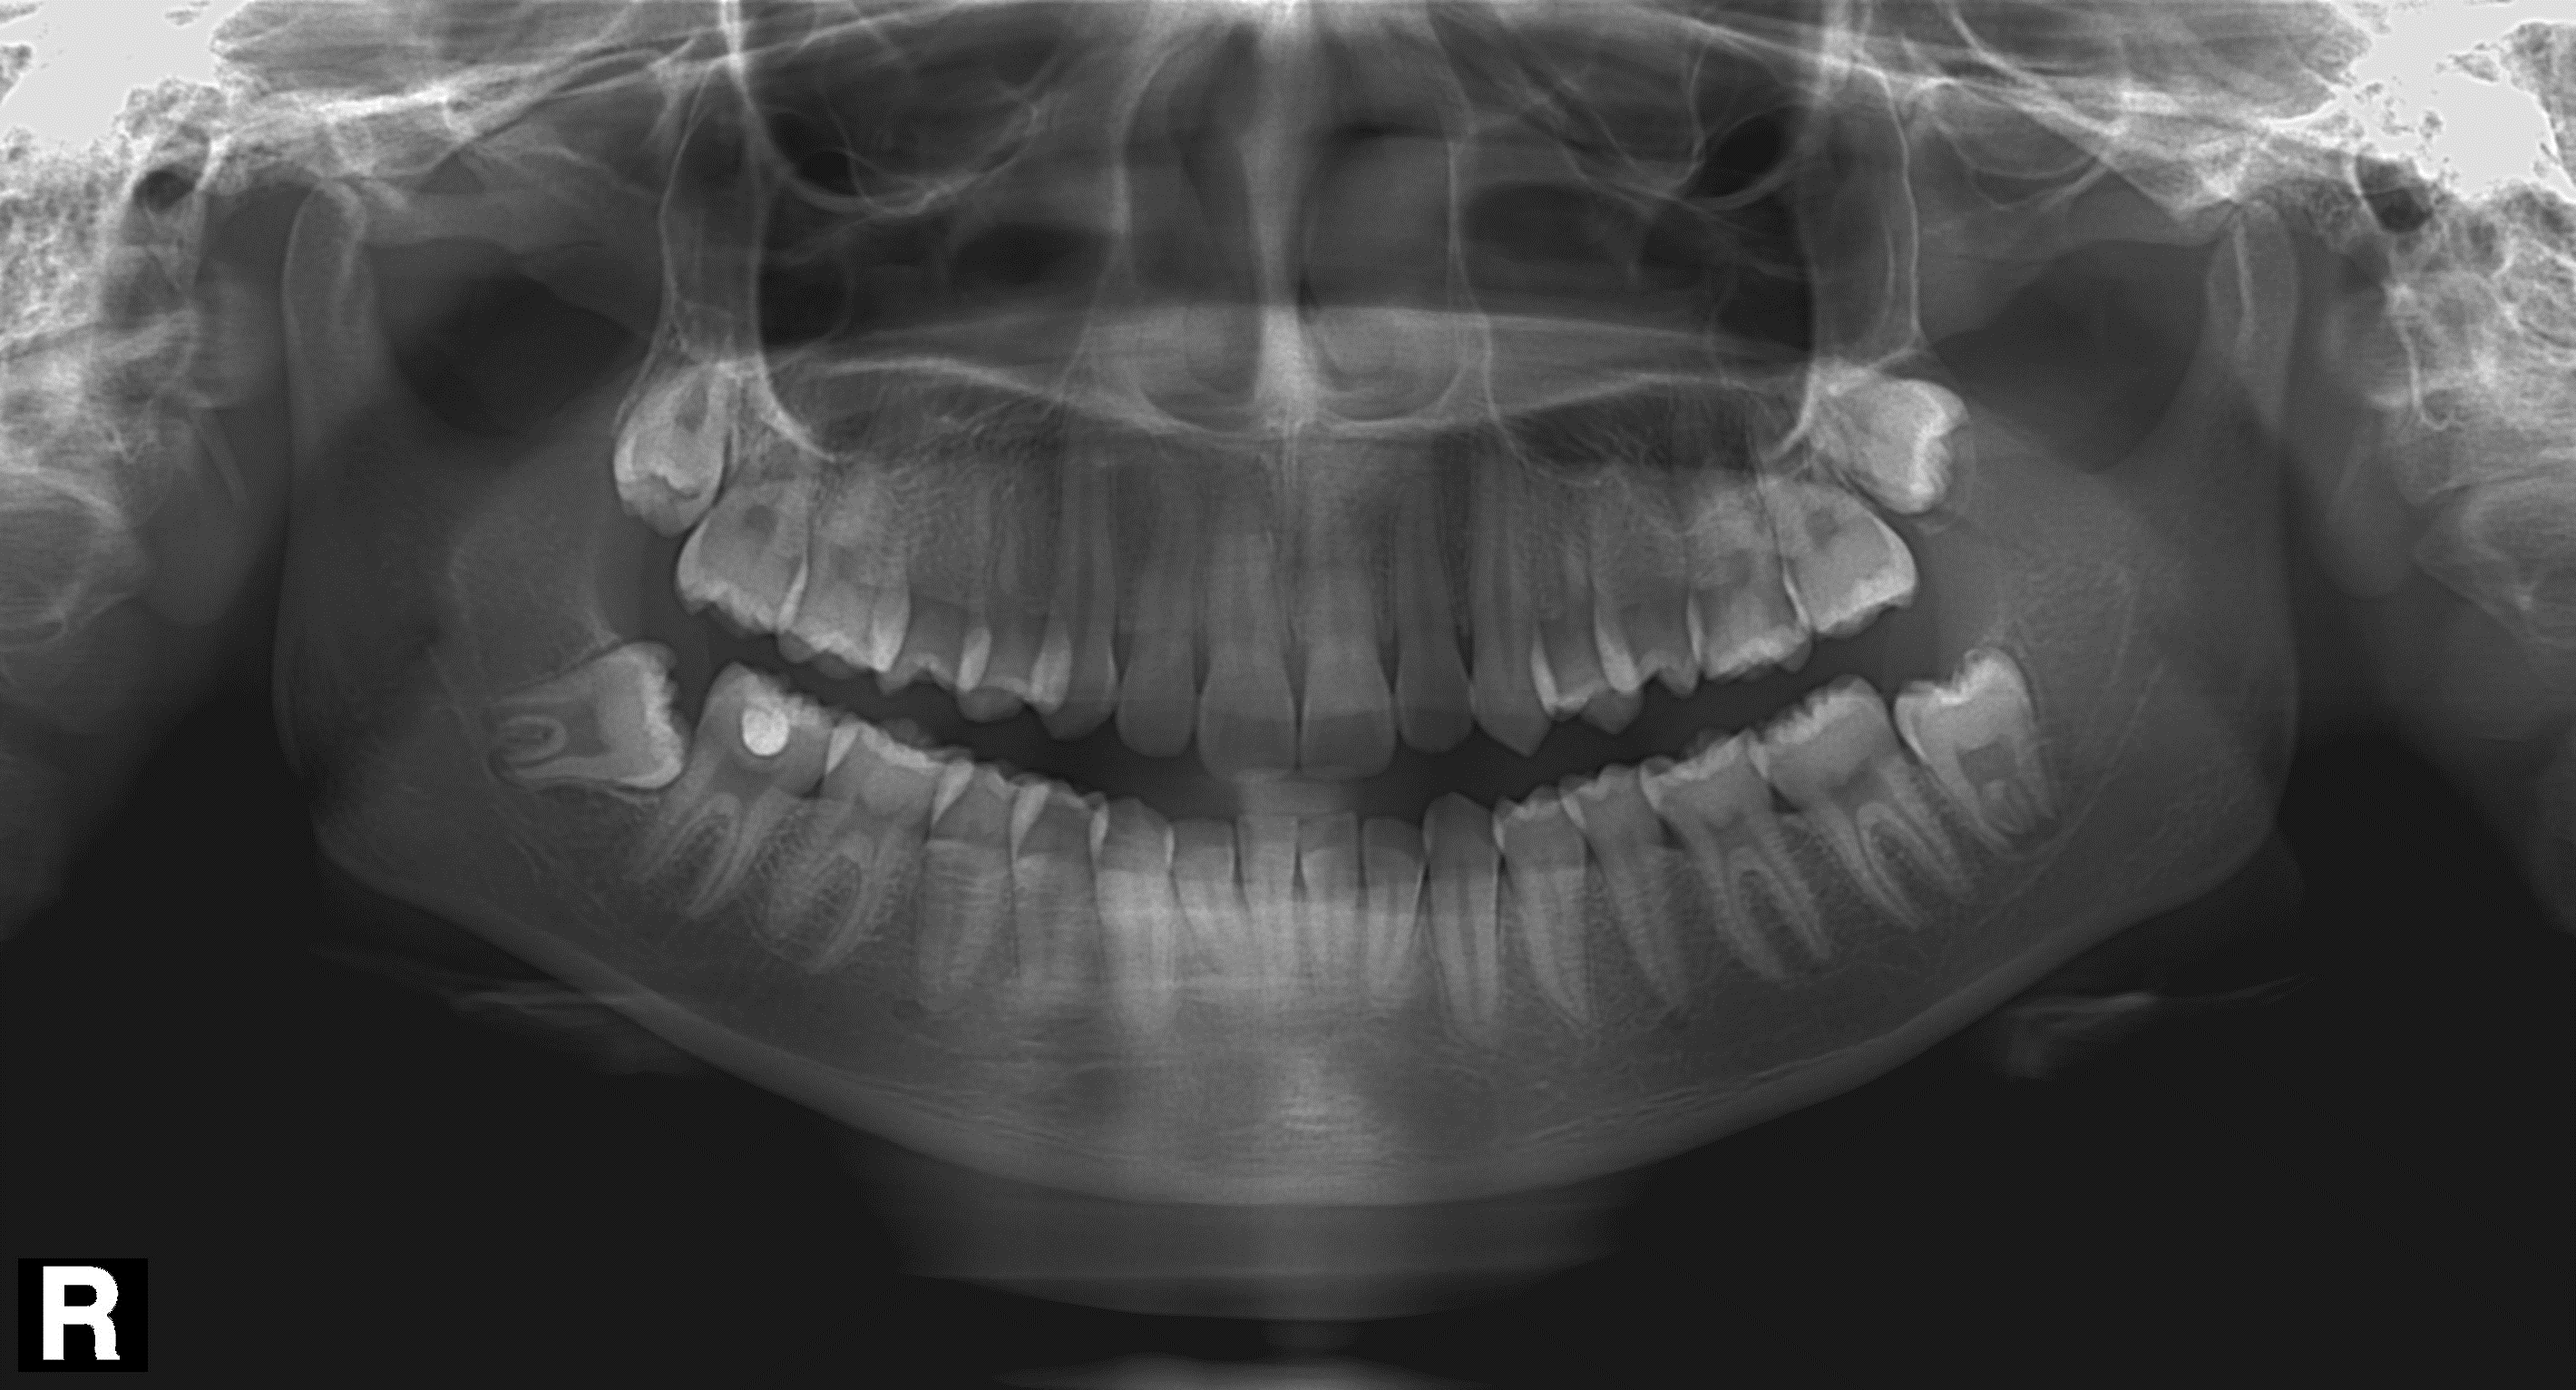

1. Суммация тени позвоночника на резцы и клыки обеих челюстей, в виде наложения белых полупрозрачных теней в середине снимка.

Рис. 1. Наложение темной тени на верхушки зубов верхней челюсти.

Одна из самых частых ошибок на снимках. Связана с положением шейного отдела позвоночника у пациента во время сканирования.

Что делать:

- Попросите пациента выпрямить шейный отдел позвоночника